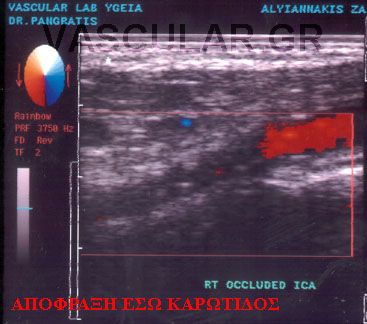

Ç Triplex åîÝôáóç ãßíåôáé áêñéâþò üðùò êáé ç Duplex åîÝôáóç ìå ôçí äéáöïñÜ üôé ç áéìáôéêÞ ñïÞ áðåéêïíßæåôáé Ýã÷ñùìç åíôüò ôïõ áããåßïõ êáé óõãêåêñéììÝíá ç öõãüêåíôñïò áéìáôéêÞ ñïÞ ( áðü ôçí êáñäéÜ) Ý÷åé êùäéêïðïéçèåß ìå êüêêéíï ÷ñþìá åíþ ç êåíôñïìüëïò ñïÞ (ðñïò ôçí êáñäéÜ) ìå ìðëå ÷ñþìá.

Ôï åðéðëÝïí äçëáäÞ óôïé÷åßï ðïõ ðñïóöÝñåé ç Triplex åîÝôáóç åßíáé ç Üìåóç áðåéêüíéóç ôïõ áõëïý ôïõ áããåßïõ ìÝóù ôçò åéêüíáò ôçò áéìáôéêÞò ñïÞò . Ç ìåãÜëç äå äéáöïñÜ ôçò Ýãêåéôáé óôçí éêáíüôçôá íá äåßîåé ôï spatial orientation ôçò áéìáôéêÞò ñïÞò. Èåùñåßôáé åðßóçò ðéü áîéüðéóôç ìÝèïäïò ãéá íá áíáäåßîåé åðéèñüìâùóç ÁèçñùìáôéêÞò ÐëÜêáò Þ ðñüóöáôï èñüìâï åðß ôïõ ôïé÷þìáôïò , ðïõ ëüãù ôçò öýóçò ôïõ õëéêïý êáé ïìïßùí õðåñç÷ïãñáöéêþí ÷áñáêôçñéóôéêþí ìå ôï áßìá äåí áðåéêïíßæåôáé óôïí Ýëåã÷ï ìå Duplex åîÝôáóç

Ç duplex - triplex åîÝôáóç ðñïóöÝñåé ÷ñÞóéìåò ðëçñïöïñßåò ãéá ôï åßäïò êáé ôçí ðïéüôçôá ôçò áéìáôéêÞò ñïÞò óå ðåñéðôþóåéò ìåñéêÞò áðïöñÜîåùò , åíþ óå ðåñéðôþóåéò ïëéêÞò áðïöñÜîåùò ðáñáôçñïýìå ôÝëåéá áðïõóßá ôçò áéìáôéêÞò ñïÞò.